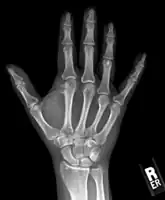

Medical imaging usually shows a well-defined wide-based bony growth on the surface of bone.[5] It can be pedunculated and irregular, giving it a "bizarre" appearance, and is not connected to underlying bone.[2]

X-ray hand, BPOP 2nd metacarpal -